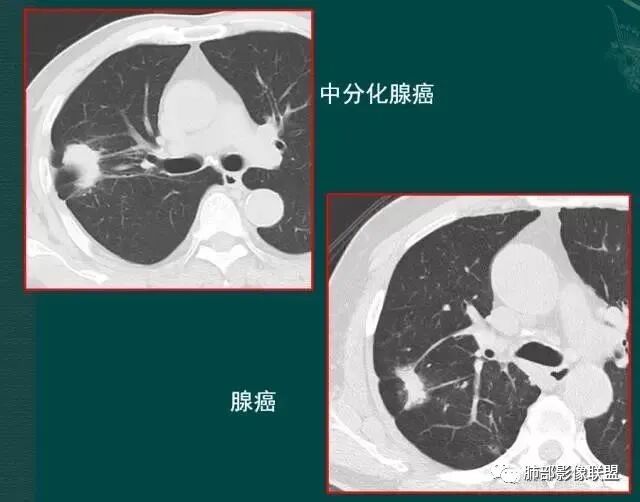

肺腺癌之—

月牙铲

在影像上观察到肿块或磨玻璃结节一侧的内凹,像个月牙铲形态,病理是肿瘤生长受到小叶间隔阻挡并受肿瘤内部的收缩力形成,王兆宇老师称之为“月牙铲”!对诊断肺腺癌较有特异性。

【肺部影像病理系列】曹舅舅告诉您影像判断肺腺癌亚型分型

【王兆宇专题讲座】普通型肺腺癌的五种生长方式

【肺部联盟影像病理系列】擒拿肺腺癌的利器----月牙铲!